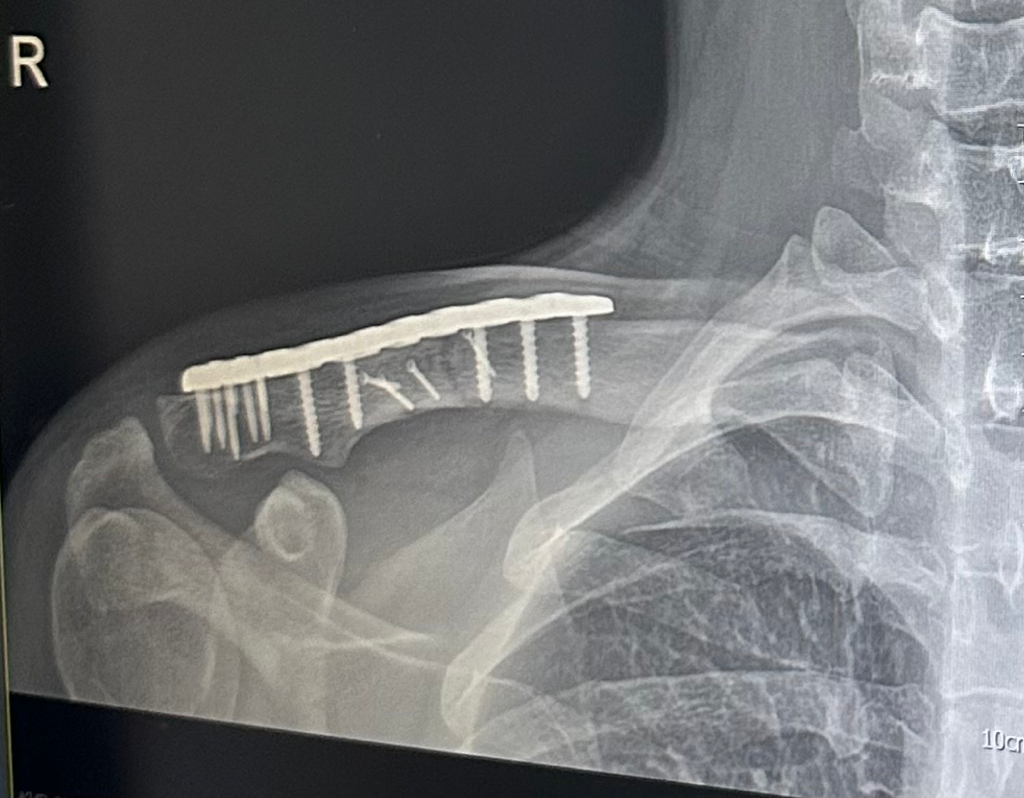

쇄골골절 수술 후 4주차입니다. 골진이 나왔는지 궁금합니다.

쇄골 골절 수술 후 4주차 입니다. 다친것은 9월24일이고 수술은 10월8일에 진행했습니다. 골진이 나왔는지 궁금합니다. 감사합니다.